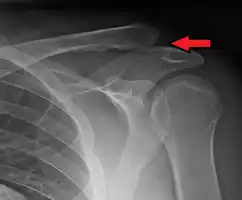

Seperated left shoulder — note that the shoulder is lower and the "piano key"; scar and screws are material from a former trauma repair

Separated shoulders often occur in people who participate in sports[5]. The separation is classified into 6 types, with 1 through 3 increasing in severity, and 4 through 6 being the most severe[6]. The most common manner of injury is a fall on the tip of the shoulder. In falls where the force is transmitted indirectly, often only the acromioclavicular ligament is affected, and the coracoclavicular ligaments remain unharmed.[7]